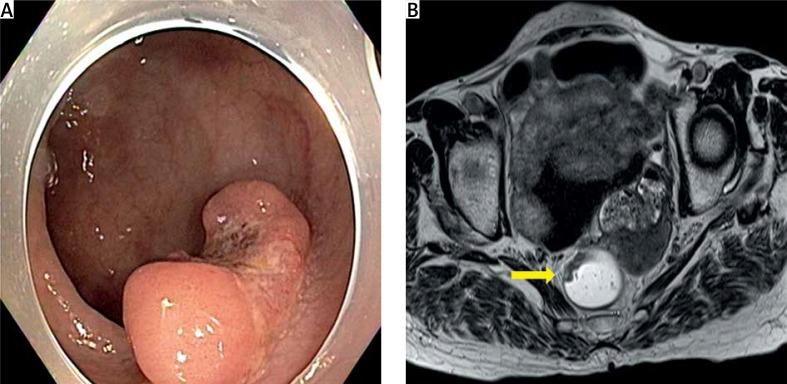

We performed a single-port plus an additional port robotic operation using a robotic single-port access through the umbilical incision, and the wristed robotic instruments were inserted through an additional robotic port in the right lower quadrant.

The total operative and docking times were 310 min and 25 min, respectively. The total number of lymph nodes harvested was 12, and the proximal and distal resection margins were 11.1 and 2 cm, respectively. The patient was discharged on postoperative day 12 uneventfully.